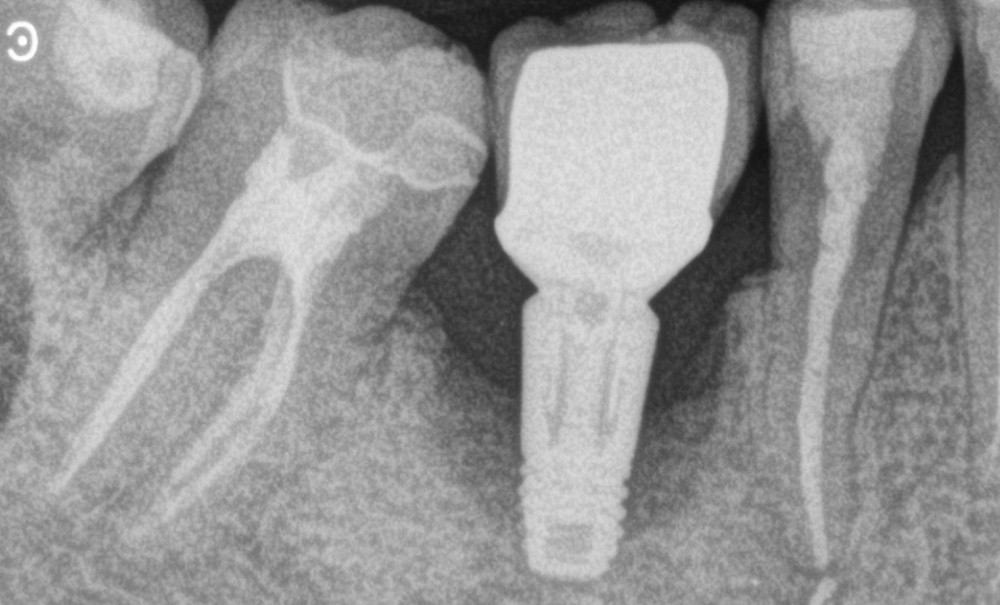

i les techniques de reconstructions osseuses trouvent toute leur place pour augmenter le volume des sites destinés à recevoir des implants, on aimerait aussi qu’elles puissent reconstruire des pertes osseuses acquises dans les situations de péri-implantite. Cette pathologie représente en effet le plus grand défi actuel en implantologie puisque 34 % des patients porteurs d’implants et 21 % des implants en service en sont atteints.

Les auteurs de cette revue narrative de littérature, parue en septembre dernier, proposent un point d’actualité sur les défis biologiques et biomécaniques à relever pour appliquer les moyens chirurgicaux de reconstruction osseuse au traitement de la péri-implantite. Pour eux, l’idée, serait de pouvoir restaurer chirurgicalement la fonction et l’architecture des tissus détruits. Mais la littérature rapporte des résultats mitigés avec un gain d’os moyen de 2 à 3 mm selon une revue systématique citée, et avec une grande hétérogénéité des résultats, loin d’être toujours atteints. Les auteurs distinguent quatre grandes catégories de paramètres en jeu dans cette procédure ainsi appliquée : la perfusion tissulaire, la topographie osseuse, la décontamination de la surface de l’implant affecté et la stabilité biomécanique du site traité.